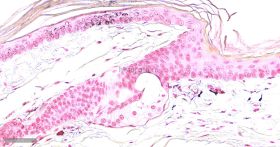

Masson-Fontana黑色素染色染色原理:

黑色素属于非血源性内生色素,是一组由黑色素母细胞产生的颜色从浅棕色到黑色的色素,这种色素通常出现在皮肤表皮、眼睛、大脑的黑质和毛囊中。黑色素有一个显著的物理性质,即完全不溶解于大多数有机溶剂--几乎可以肯定是由于黑素体中已形成的黑色素可与蛋白质紧密结合;黑色素另一个物理性质是能够被强氧化剂漂白,尽管这个过程是缓慢的,在病理情况下,这种色素也可出现在良性痣细胞瘤中和恶性黑色素瘤中,在常规HE染色中不呈黑色而是呈棕黄色或棕黑色,许多方法可用于识别黑色素和黑色素生成细胞,如还原方法,如Masson-Fontana银技术和Schmorl三价铁-铁氰化钾还原实验;酶方法(如多巴反应);荧光方法:免疫组织化学。

Masson-Fontana黑色素染色液是利用黑色素具有将银氨溶液还原为金属银特性即嗜银反应原理来显示黑色素,染色后黑色素呈黑色,该法属于常用的黑色素特殊染色法,效果较其他染色理想。

染色结果: